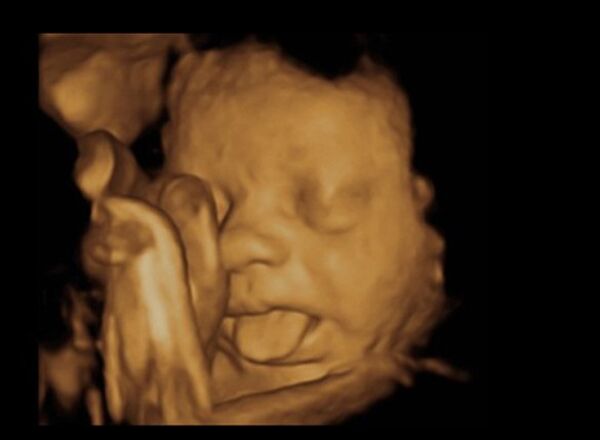

Bebekler anne karnında ne yapar?